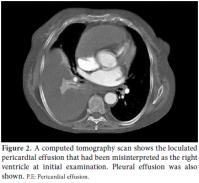

Our case involved a 61-year-old female patient who had been diagnosed with seropositive and erosive RA 20 years previously. She had no extraarticular involvement and was using oral methotrexate 15 mg once a week. The patient was admitted to another hospital having complained of progressive dyspnea, chest pain, and lower leg edema for more than 10 days. Pericardial effusion was detected by a thoracoabdominal computed tomography (CT) scan, and she was transferred to our hospital. At arrival, physical examination showed an arterial pressure of 110/70 mmHg, a pulse rate of 120 beats/min, a respiratory rate of 30/min, and a body temperature of 37 °C with distended neck veins, mild hepatomegaly, and decreased heart sounds. The patient did not have arthralgia, and there were no signs or symptoms related to active RA. Electrocardiography (ECG) revealed atrial fibrillation with high ventricular response and low voltage. A chest X-ray showed cardiomegaly with clear lungs. Laboratory investigations showed a C-reactive protein level of 129 mg/L, a sedimentation rate of 8 mm/h, a plasma D-dimer measurement of 998 ng/mL, a white blood cell (WBC) count of 11.500 cells/mm3, a platelet count of 428.000/mm3, and a moderate degree of anemia. A transthoracic echocardiogram (TTE) demonstrated a near total collapse of the right atrium and the right ventricle due to compression by an adjacent cystic structure covered with a thick membrane (Figure 1). When we examined the CT scan in light of these echocardiografic findings, we noticed that this large cystic structure had been misinterpreted as the right ventricle (Figure 2). On the CT scan, we found a bilateral pulmonary embolism but no masses or lymphadenopathy suggestive of malignancy. A color Doppler ultrasonography was performed which revealed the source of the embolism to be the presence of bilateral deep vein thrombosis at the lower extremity. Since the patient was symptomatic, surgery was planned. Surgical exploration via an anterolateral thoracotomy showed a viscous loculated material compressing the right ventricle and the right atrium anterolaterally along with a thickened pericardium. The surgeon also noted the fibrous thickening which caused septation and compartmentation of the pericardium and a 1500 cc hemorrhagic jelly-like fluid drainage. Analysis of the fluid revealed a pH of 7.15, a WBC count of 115/mm3 (predominantly lymphocytes), a protein level of 5.8 g/dl, an LDH level of 780 U/L, and a glucose level of 2 mg/dl. A pathologic examination of the pericardial material revealed prominent infiltration with lymphocytes and plasma cells, which correlates well with chronic inflammation. Bacterial cultures and a polymerase chain reaction (PCR) test for Mycobacterium tuberculosis were all negative with no malignant cells on cytological examination. Both the pathologic specimen and the pericardial fluid had no findings consistent with tuberculosis and malignancy. The Mantoux test was also negative.